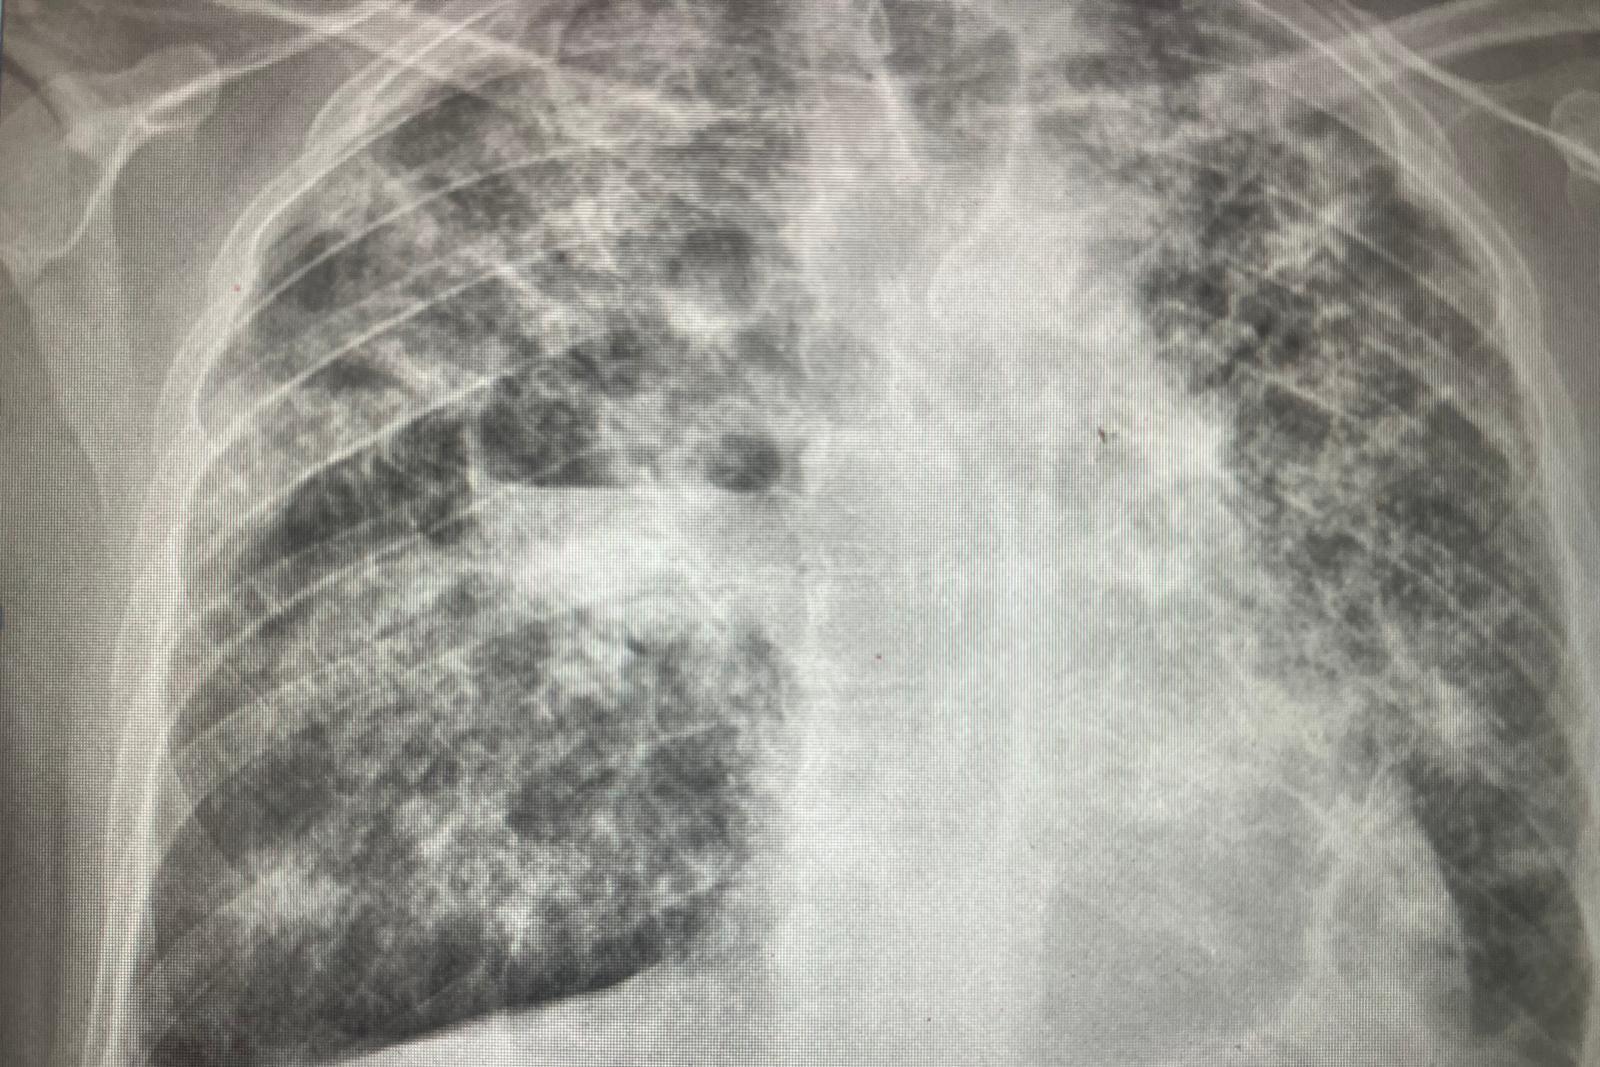

Tuberculosis can cause irreversible damage to the lungs - the white marks on this X-ray show the effects of the disease

However, if left untreated, the illness can cause irreversible damage to the lungs.